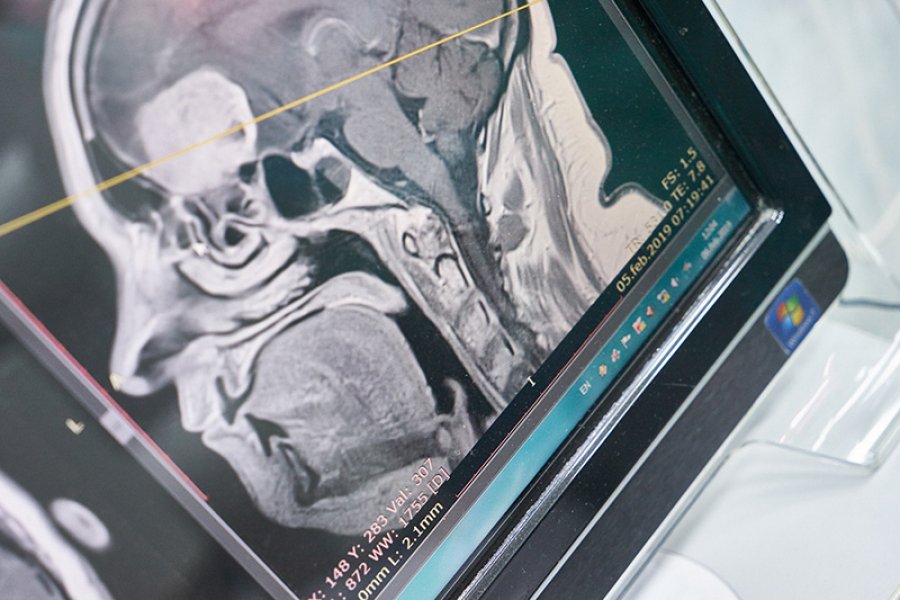

Direktor Klinike za neurohirurgiju, Novak Lakićević, pojasnio je da se radi o savremenom neurohirurškom aparatu koji se koristi za operacije tumora mozga i kičmene moždine, a kojim će, kako je rekao, biti olakšano precizno i uspješno uklanjanje tumora.

„Njegova funkcija je da ultrazvukom usitni tumorsko tkivo, istovremeno ga aspirira, čuvajući okolne velike krvne sudove, što nama značajno pomaže da što efikasnije uklonimo tumor od zdravog moždanog tkiva“, objasnio je Lakićević.